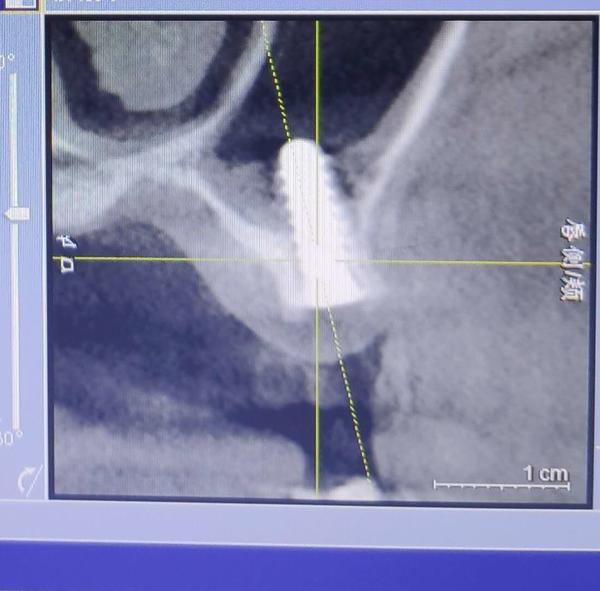

2019年下半年,在出现了不适反应后,叶女士到沈阳一家部队医院口腔门诊求医。经CT等检查,她才发现,原来有一颗种植体已经进入了她的上颌窦腔。

叶女士做出的影像检查结果显示,其中一颗植体已经进入上颌窦腔内。

“有大医院医生告诉我,这就是说,种植体把我上颌窦腔打穿,口腔和鼻腔连通了!”叶一帆说,她随后了解得知,袁克伟并不具备种植牙的技术水准,而且执业地点也不在天丽口腔,且天丽口腔诊所也不具备种植牙这一诊疗项目,“我是被他当成小白鼠了”。

2019年7月,在出具的诊断证明上,沈阳市当地一家三甲医院的知名口腔诊疗专家说,该种植体已经进入上颌窦腔,需要取出。